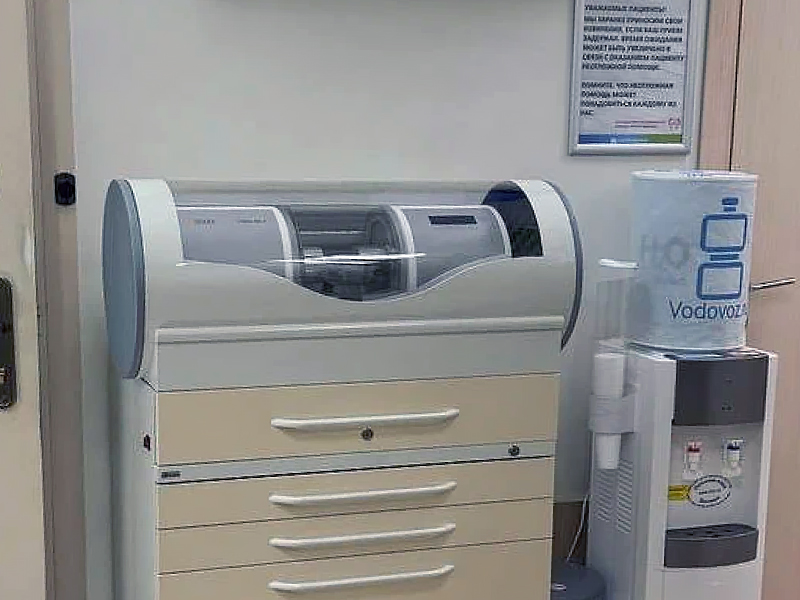

Наше оборудование